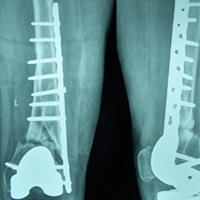

Case:8 Polytrauma

Patient having closed segmented fracture midshaft & lower 1/3 Tibia with closed fracture superior & inferior pubic rami right side with pelvis fracture following vehicular accident wastreated with intramedullary nail for fracture tibia and external fixator for fracture pelvis.

Pre-Op

Immdiate Post-op

Ex fix with frame